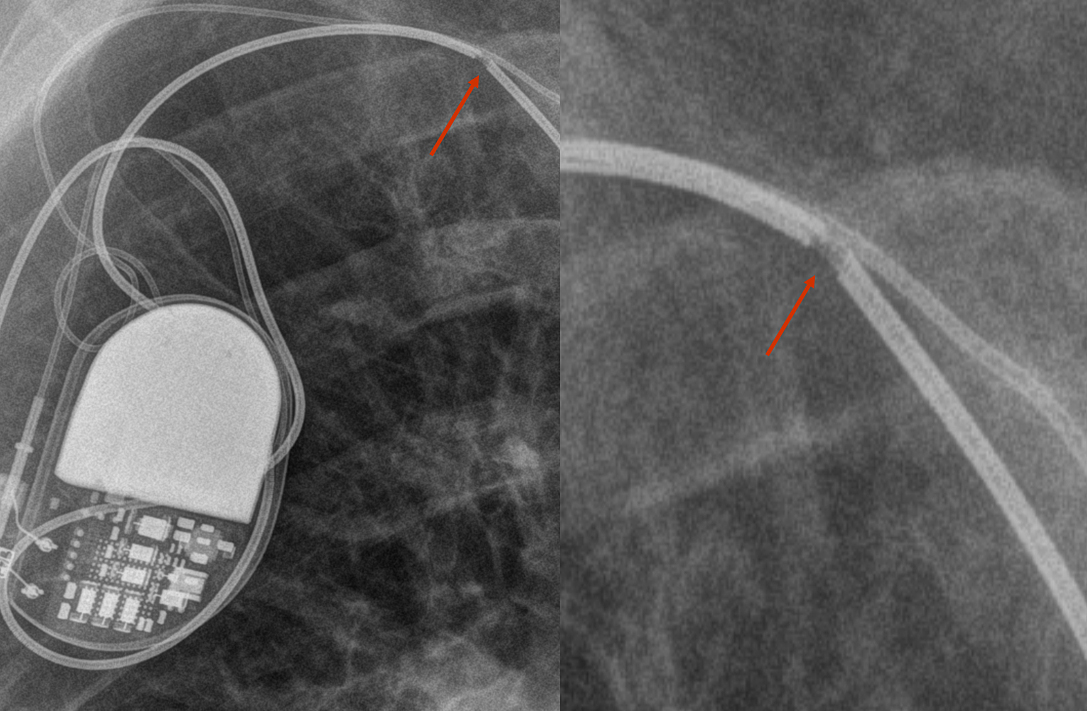

PM lead - broken